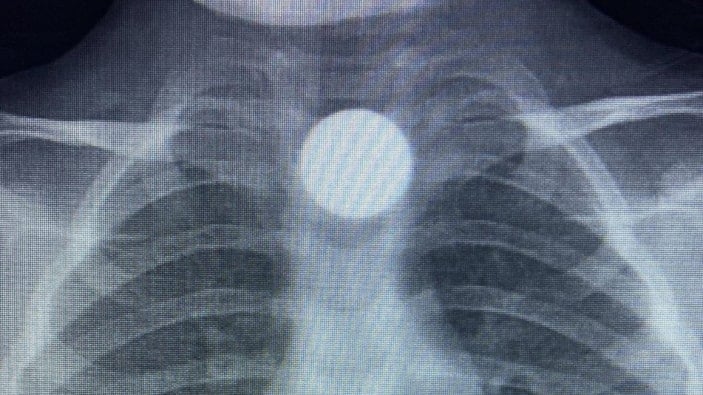

Çocuğun parayı yuttuğunu fark eden ailesi, Bilal K.’yi vakit kaybetmeden özel araçla İnegöl Devlet Hastanesi’ne götürdü. Hastanede yapılan muayene ve görüntüleme işlemlerinde, madeni paranın çocuğun yemek borusunda takılı kaldığı tespit edildi.

İlk müdahalesi İnegöl Devlet Hastanesi’nde yapılan Bilal K., ileri tetkik ve tedavi amacıyla ambulansla Bursa Yüksek İhtisas Eğitim ve Araştırma Hastanesi’ne sevk edildi.